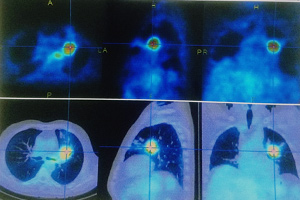

Detección temprana de cáncer de pulmón

Mediante perfiles de actividad metabólica en inmunobiopsia líquida